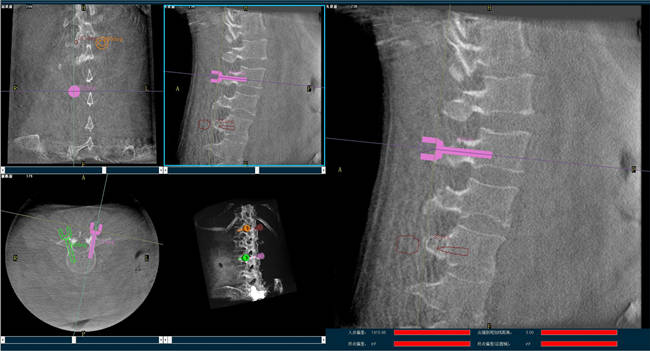

迄今,術(shù)前規(guī)劃已經(jīng)成為骨科手術(shù)的“前哨守衛(wèi)”,目前的脊柱外科手術(shù)機(jī)器人可以通過人工智能算法做到精準(zhǔn)的脊柱分節(jié)段識別并模擬重現(xiàn)患者的生理特征與骨骼排列,讓手術(shù)既準(zhǔn)確又安全;尤其在脊柱外科手術(shù)中可以發(fā)揮很大作用,避免產(chǎn)生對周圍神經(jīng)、椎管內(nèi)脊髓的損害,減少并發(fā)癥的出現(xiàn)。

以椎弓根螺釘置入手術(shù)為例,有時候?yàn)榱藴?zhǔn)確定位,甚至需要將椎弓根螺釘多次進(jìn)出、反復(fù)選擇,這樣無疑就增加了脊髓神經(jīng)損傷的風(fēng)險,降低了螺釘把持力。但脊柱外科手術(shù)機(jī)器人可以在術(shù)前規(guī)劃把手術(shù)入路、方向、釘子的深度都做好規(guī)劃,手術(shù)前就在電腦上規(guī)劃好進(jìn)釘?shù)奈恢茫谑中g(shù)中利用機(jī)器人系統(tǒng)“(脊柱)分節(jié)段單椎體識別”、“釘棒一體化”、“術(shù)中全程可視”等特性,做到“一步到位”,因此,比起傳統(tǒng)手術(shù),機(jī)器人手術(shù)更加安全。同時,目前機(jī)器人技術(shù)的透視檢查時長、每顆螺釘置入時長和住院時長均比術(shù)中使用3D-CT導(dǎo)航更短,提升手術(shù)效率。